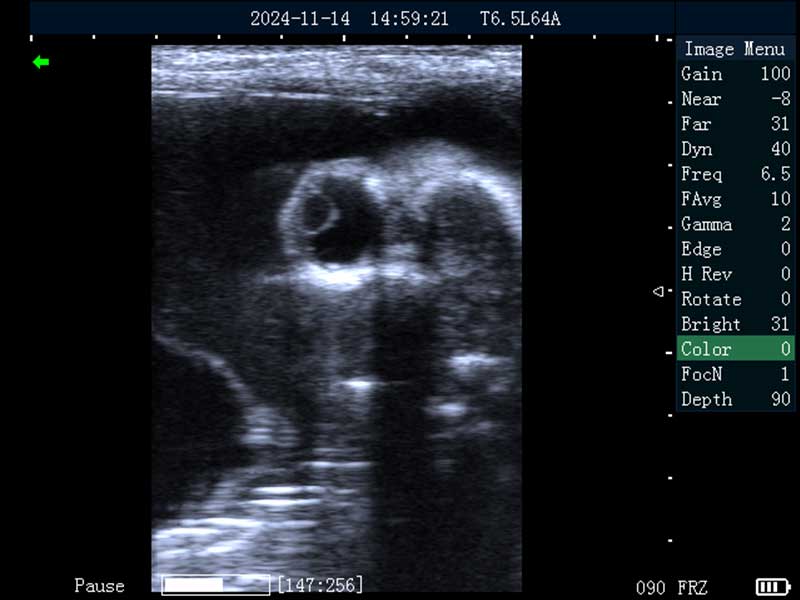

牛卵巢

牛妊娠40日龄

牛妊娠65日龄